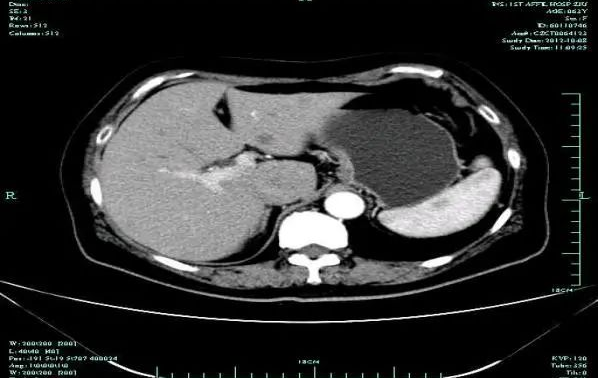

CT-T

CT-H1

MR-H1

影像学检查结果评估:cPD。

• 第三次FOLFOX+T方案后 B超提示肝转移灶消失

疗效评估:cPR